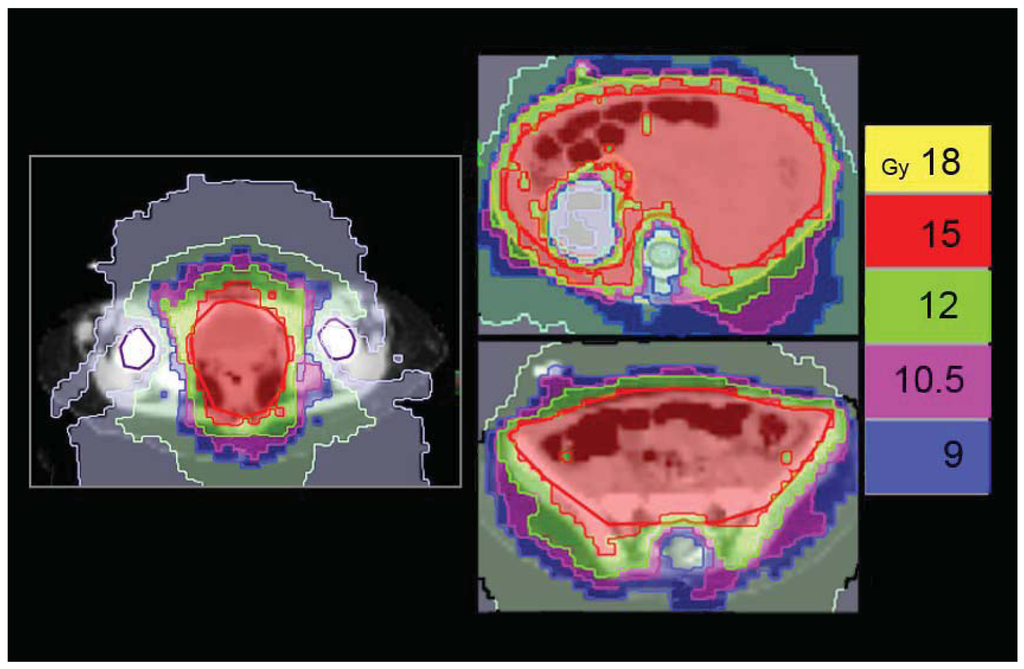

Finally, HT gives us the opportunity to re-treat areas that have been already treated. The advantages for re-treatment with HT are the greater conformality of dose distribution and the possibility to respect dose constraints for adjacent, critically sensitive, previously irradiated normal tissues. This opportunity could be of interest both for palliative intent and for patients in which curative treatment could not be obtained with other procedures. We use HT for the re-treatment of local relapsed brain tumors and “in field” relapsed Hodgkin lymphomas. Both these situations can adequately be managed by other techniques like Linac-delivered IMRT or stereotactic treatment. An unusual condition in which HT can play a specific role is the re-irradiation of the craniospinal axis. We employed this technique in a 10-year-old male with diffuse meningeal spread of disease, 24 months after the first-line CSI for a standard risk medulloblastoma, proved to be refractory to salvage chemotherapy. He received 23.4Gy in 13 fractions to the craniospinal axis, with a reduced dose to posterior fossa of 18Gy. HT allowed us to adequately re-treat the entire axis, while giving a safe dose to the posterior fossa, previously treated by the full dose (55.8Gy).